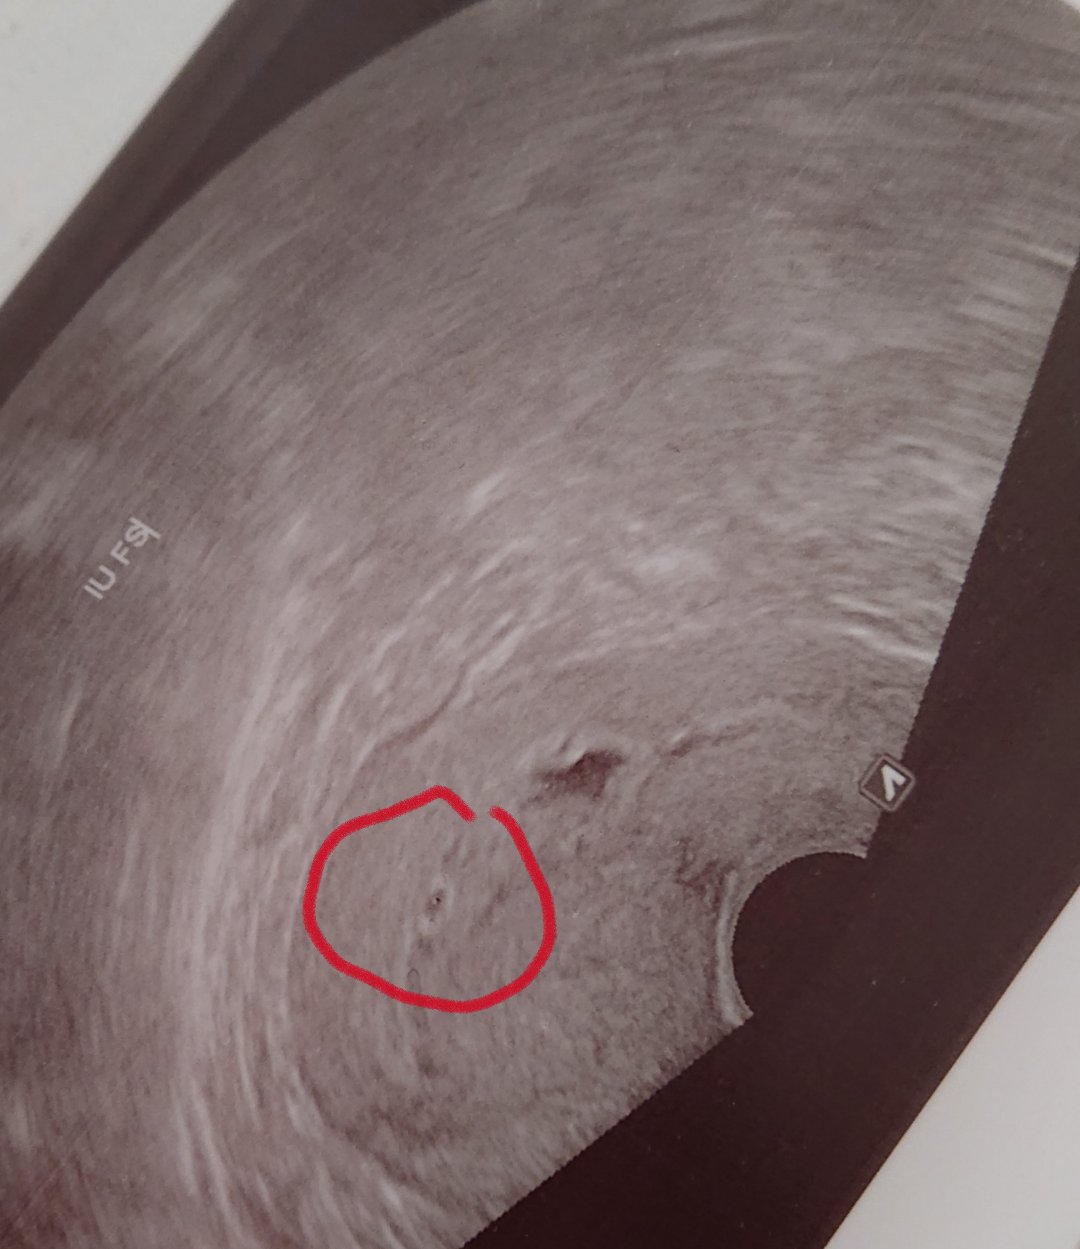

Som tehu 4-6tt, doktor mi tehotenstvo nepotvrdil, nakoľko na sone nevidel vôbec nič ( minuly týždeň).

@supucka ahoj, chcem sa ta spýtať, v ktorom týždni ti bolo vidieť už plod? Mne naposledy bolo vidieť už aj zltkovy vak, som 6+5tt cca ale plod zatiaľ ešte nevideli na sone ( včera ma pohotovosti) .

@supucka aj ja som mala taký podobný GS a v ňom zltkovy vak, ten sa mi ešte len teraz musel spraviť niekedy? Lebo predtým mi lekár vravel že vidi len gs.. tak ja neviem 😁 a v stredu idem opäť na kontrolu a to už budem presne v 7tt, tak hádam už bude vidieť🙂

Ahoj, tak asi mame plodik, síce ešte mini ale doktor povedal, že ho vidí. Boze🙏ja sa celá klepem. O týždeň kontrola. A ty ako?

Neboj, bude dobre uvidíš. Véd si mala už ten žĺtkov vak. Mne teraz videl fakt niečo malé, snažil sa to rozlúštiť a popritom mi to hovoril. Ze podľa neho vidí plodik a aj ze sa mu zdá ze tam dačo bliká, tak to som odpadla. Ale povedal, že treba čakať. Ale podla hcg a progesteronu to vyzerá na zdravé vnutromaternicove tehotenstvo. Hcg mi brali v pondelok a teraz boli výsledky 62000tusim bolo. Ale ja mam aj cystu a vedľa nej sa robí ďalšia dúfam. Lebo povedal ze je veľmi veľmi veľmi malá pravdepodobnosť až 1%k niekoľko tisíckam že by išlo súbežne aj o mimomaternicove.

@tmtm ahoj, tak bola som na tej kontrole a tiež už videl mimi ale veľmi malinké, ale zatiaľ všetko ok 😊 len srdiečko ešte nepostrehol, ale tak možno je ešte skoro.. aaa mala by som byt v nejakom 6tt 😊 a na kontrolu teraz idem až o tri týždne